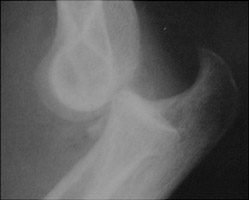

Coronoid process fractures are associated with posterior elbow dislocations. Generally an isolated coronoid process fracture is rare; most will have associated radial fractures. Recent authors have proposed the use of the radial head-capitellum view for the diagnosis of this injury.

- Click on the image for a larger versionALateral radiograph of the elbow. There is a posterior dislocation of the elbow with a fracture of the coronoid process.